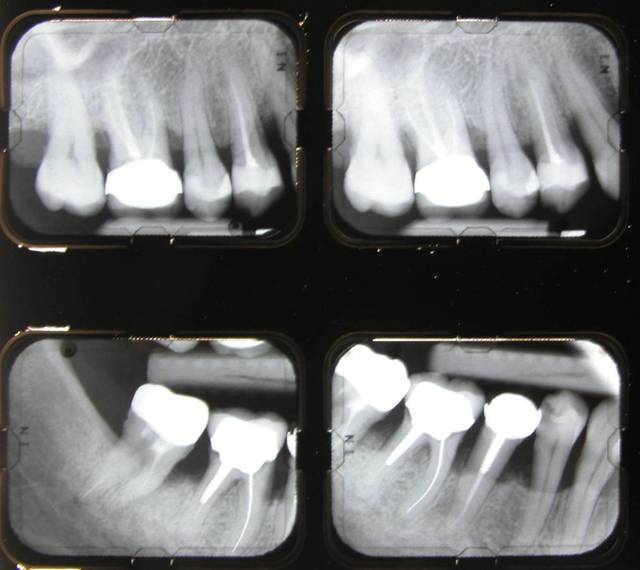

Voici le cas d'une patiente que j'ai traité pour une parodontite chronique.

Donc il s'agite d'une patient adressée par un confrère pour un avis paro avant un traitement ODf. La patiente a cinquante cinq ans. Elle fume des cigares, des problèmes d'hygiène. Je dignostique une parodntite chronique que j'ai traité en non chirurgical. La patiente est en observation avant d'entamer un traitement prothétique plutôt qu'ODF.

Pour me faire pardonner, je vous envoie le status initial et le bilan de sondage.

Je ne vois pas où le protocole est incomplet. Par contre j'attendais la question microbio. Pour ma part ayant travaillé dans un laboratoire de microbio, je peux dte dire que je n'ai pas besoin d'un prélèvement pour poser un diagnostic. Je n'avais pas à prescrire d'antiobios dans ce cas là, donc pas d'antibiogramme.

Après le traitement, on a une flore compatible avec la santé gingivale, présence de bactéries du complexe vert, quantité 2.6x10-3. Absence de bactéries mobiles, population de cocci, et pour les amateurs d'amibes tout va bien.